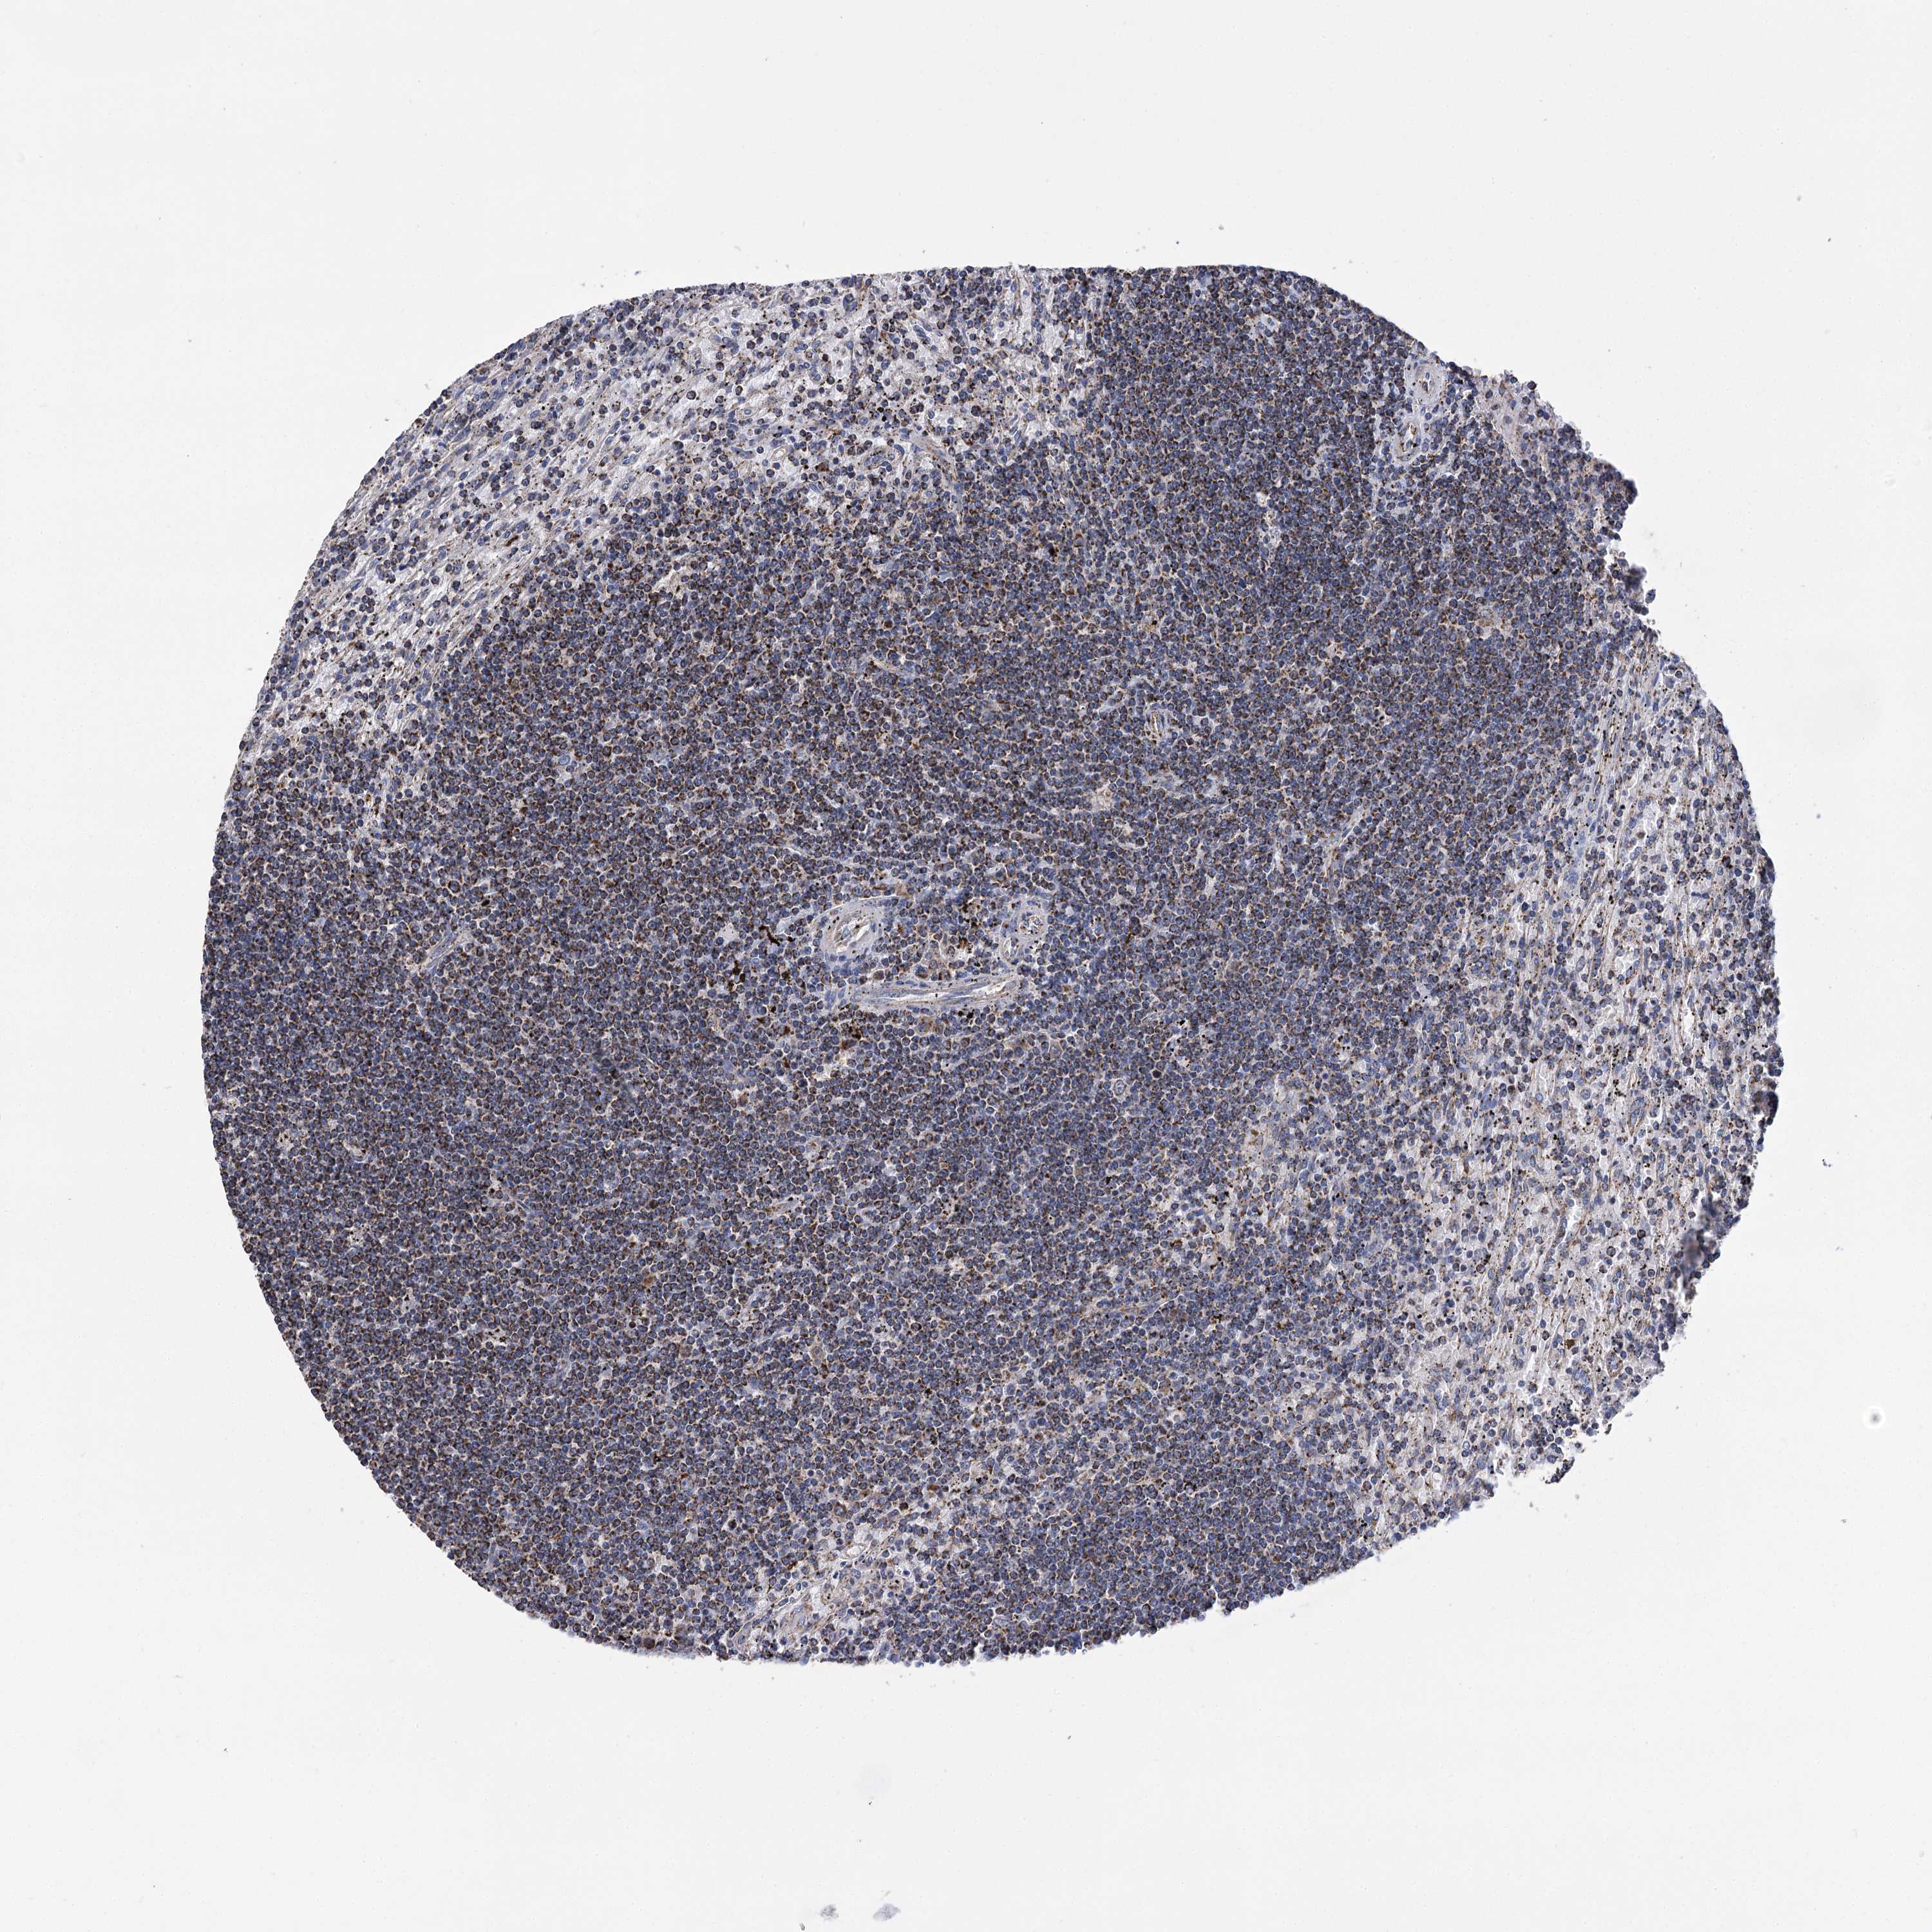

CANCER LYMPHOMA Show tissue menu

LYMPHOMA - Protein expressioni

A mouse-over function shows sample information and annotation data. Click on an image to view it in a full screen mode. Samples can be filtered based on level of antibody staining by selecting one or several of the following categories: high, medium, low and not detected. The assay and annotation is described here.

Each image is clickable and will lead to virtual microscopy that enables deeper exploration of all samples and also displays staining intensity scores, fraction scores and subcellular localization as well as patient and tissue information for each sample.

Antibody HPA038668

Antibody HPA038669

Hodgkin's disease, NOS

Malignant lymphoma, non-Hodgkin's type, High grade

Malignant lymphoma, non-Hodgkin's type, Low grade